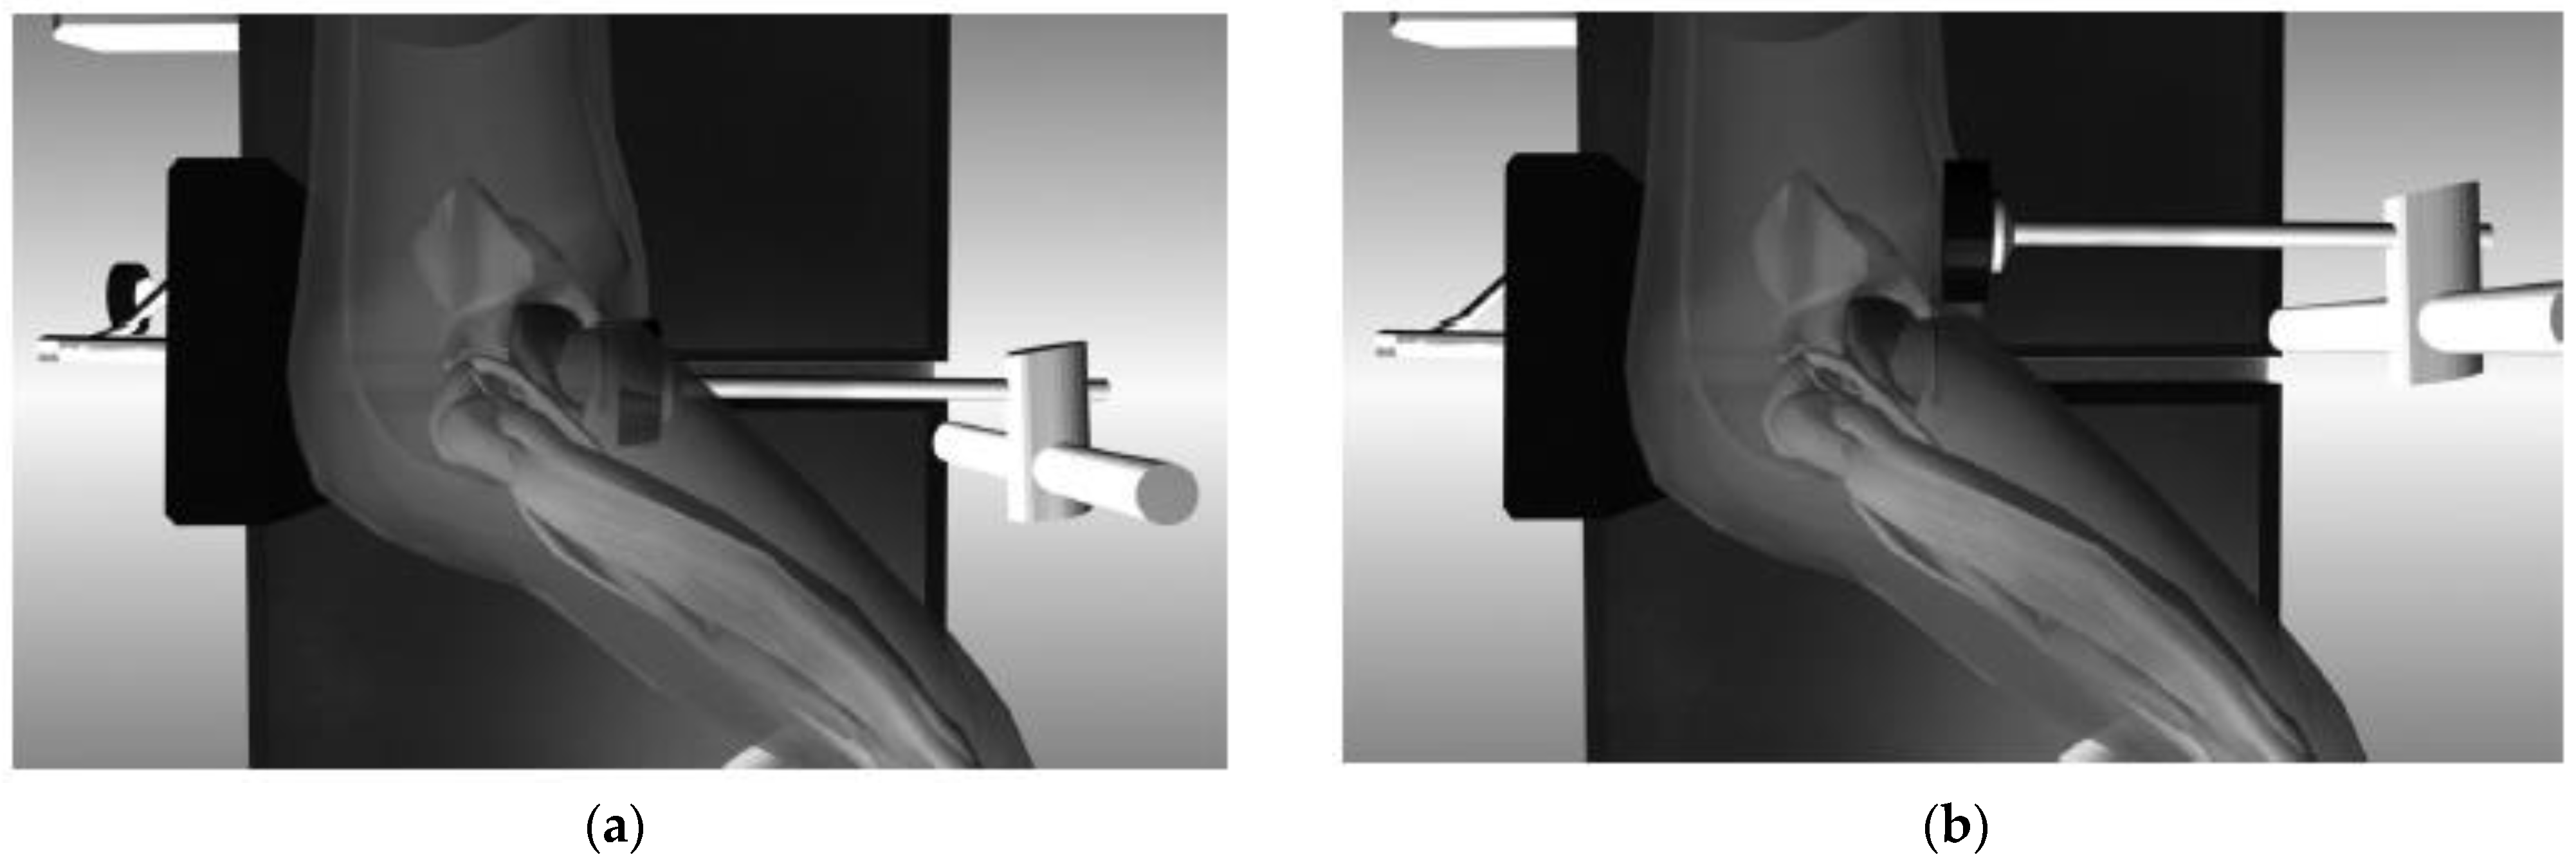

The orthopedic position used in “hip replacement surgery” can be adopted to avoid this impediment (Figure 2a). We decided to proceed with this new method in all cases where the patient’s head rotation was less than 130 degrees (Figure 2b).

Figure 2. (a) Patient decubitus in “orthopedic position”; (b) patient’s head rotation less than 130°.